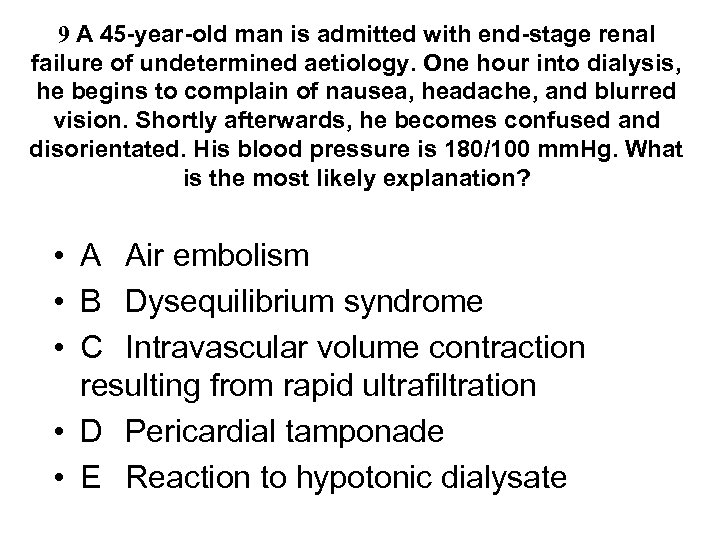

Reflux nephropathy • Treatment • - RCTs have shown equal efficacy of continuous antibiotics until puberty and ureteric reimplantation in children with reflux and UTI - reimplantation now less common than before • - prophylactic antibiotics for asymptomatic infection now no longer recommended after puberty • - only patients with serious recurrent UTI or pyonephrosis require nephrectomy before transplantation (bilateral nephrectomy not routine) • Outcome • - combination of reflux and UTI usually required to cause scarring and CRF • - but new scars rarely develop after 8 yrs of age • - progressive loss of renal function, invariably assoc with HT and proteinuria, can occur in absence of both UTI and reflux if GFR<50 ml/min • - CRF not caused by recurrent acute pyelonephritis - UTI present in a minority of adults • - accounts for ~ 20% cases ESRD requiring dialysis (not 50%)

Reflux nephropathy • Treatment • - RCTs have shown equal efficacy of continuous antibiotics until puberty and ureteric reimplantation in children with reflux and UTI - reimplantation now less common than before • - prophylactic antibiotics for asymptomatic infection now no longer recommended after puberty • - only patients with serious recurrent UTI or pyonephrosis require nephrectomy before transplantation (bilateral nephrectomy not routine) • Outcome • - combination of reflux and UTI usually required to cause scarring and CRF • - but new scars rarely develop after 8 yrs of age • - progressive loss of renal function, invariably assoc with HT and proteinuria, can occur in absence of both UTI and reflux if GFR<50 ml/min • - CRF not caused by recurrent acute pyelonephritis - UTI present in a minority of adults • - accounts for ~ 20% cases ESRD requiring dialysis (not 50%)

18 With regard to lupus nephritis: • A It may present with a rapidly progressive glomerulonephritis • B It may present with histological changes similar to diabetic nephropathy • C It should be treated with oral steroids alone when associated with a membranous histology • D It should only be treated with cytotoxic agents when serum creatinine > 120 mol/l • E Frequently complicates drug induced SLE

18 With regard to lupus nephritis: • A It may present with a rapidly progressive glomerulonephritis • B It may present with histological changes similar to diabetic nephropathy • C It should be treated with oral steroids alone when associated with a membranous histology • D It should only be treated with cytotoxic agents when serum creatinine > 120 mol/l • E Frequently complicates drug induced SLE